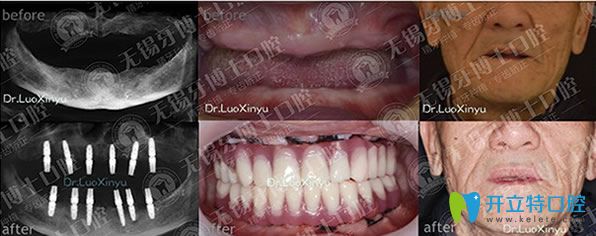

牙博士口腔種牙好不好,樸東信院長全口種植牙代表案例:

牙博士口腔樸東信院長全口種植牙代表案例

無錫牙博士口腔樸東信院長,種植牙技術(shù)適用于各種缺牙類型,美觀舒適,媲美真牙,咀嚼功能強(qiáng),種植牙后,想要具有和天然牙一樣的功效,長期使用,需要保持良好的口腔衛(wèi)生。